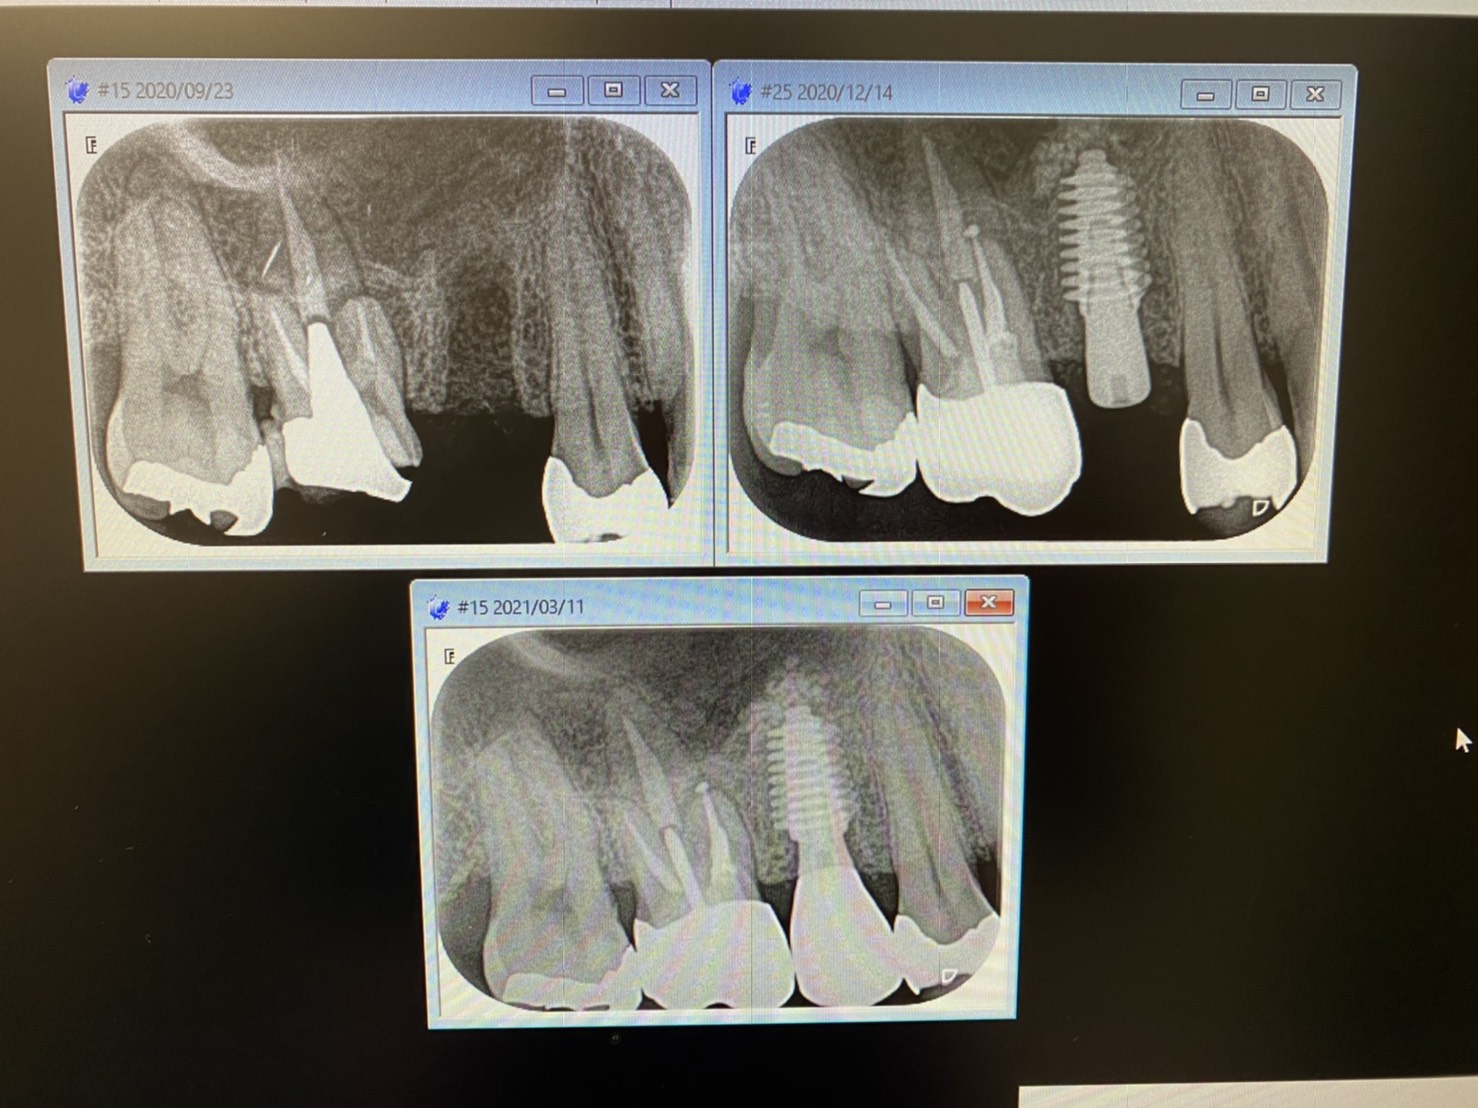

本日は、昨年12月にソケットリフト併用のインプラントオペされた方の上顎5番の最終補綴物のセット。

オペから完成まで3ヶ月かからずのスピード感

以前のプロトコールでは上顎は6ヶ月間、下顎は3ヶ月間と言われ、噛めるようになる迄には1〜2年がかり…『苦痛だよ』と耳にします。